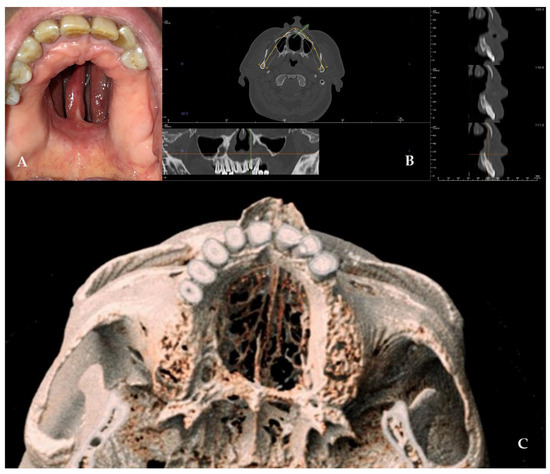

A 49-year-old female patient came to our attention in 2021, presenting a palatal/oro-nasal fistula measuring 2 cm in diameter along the major axis and with atrophic and burned soft tissue surrounding the lesion (Ia according to the Okay et al. classification [14]).

The patient was treated with an obturator to permit correct speech and feeding. At the clinical and radiographic examination, there was also wide, bony, and cartilaginous septal destruction with communication of the nasal cavity and collapse of the nasal pyramid. Speech disturbances, rhinolalia, and eating difficulties were observed (Figure 1).

Figure 1. (A,B) Clinical presentation of the oro-nasal communication. In inset (A), it is possible to appreciate the collapse of the nasal pyramid. (C,D) Radiographic and 3D reconstruction using InVivo6® and Anatomage Table EDU vers.8® (Santa Clara, CA, USA) software. DICOM files were imported in InVivo6® (Santa Clara, CA, USA) software to obtain the axial, cross, and panorex sections. Afterwards, the DICOM files were imported Anatomage Table EDU vers.8® (Santa Clara, CA, USA) to obtain the 3D rendering.